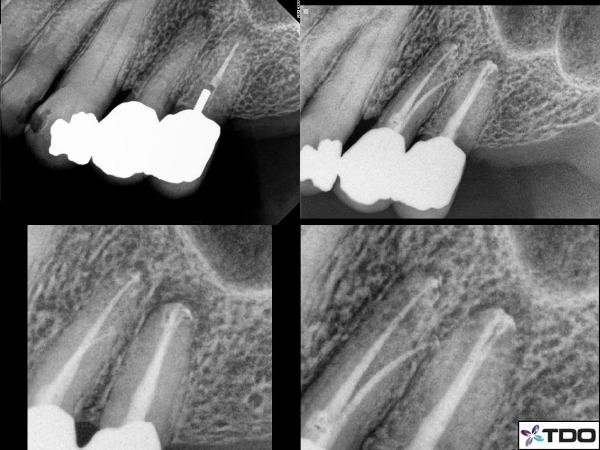

Had I completed that case a few weeks ago at the initial appointment I would not have found that 4th canal. What ultimately I needed was more time. This is not at all uncommon. Here is an example in figure 1 in which it took 4 appointments to find all of the canals and complete the treatment. Tooth #12 was highly calcified and tooth #13 had an extra canal with a deep apical split. There is no room for error with these teeth and thus taking the N-step endodontic approach was critical.

Figure 1: This case has all the elements of why a multi-visit approach was necessary. Both #12 and #13 were infected and the swelling was present over both roots and confirmed radiolucency of both teeth with a CBCT. At the first visit I removed the post of #13 and shaped the canal. I accessed #12, but did not find either canal. The second visit the swelling was only about 50% improved. I then found the buccal canal of #12 and the apical split of #13 to the second canal. The 3rd visit the swelling was fully resolved, and I finally found the palatal canal of #12. I then completed the case entirely on the 4th appointment.